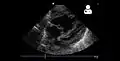

Echocardiography

If pulmonary hypertension is suspected based on the above assessments, echocardiography is performed as the next step.[12][14][55] A meta-analysis of Doppler echocardiography for predicting the results of right heart catheterization reported a sensitivity and specificity of 88% and 56%, respectively.[57] Thus, Doppler echocardiography can suggest the presence of pulmonary hypertension, but right heart catheterization (described below) remains the gold standard for diagnosis of PAH.[12][14] Echocardiography can also help to detect congenital heart disease as a cause of pulmonary hypertension.[12]

- 4-month-old with pulmonary hypertension as seen on ultrasound[58]

4-month-old with pulmonary hypertension as seen on ultrasound[58]- Long standing pulmonary hypertension[59]